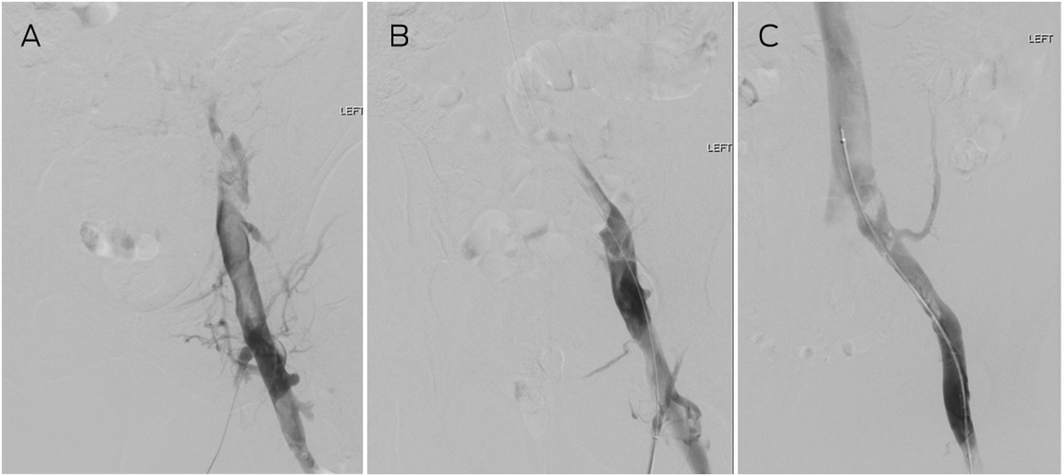

Box 1 – Thrombolysis for acute bilateral proximal deep vein thrombosis*

* (A) Venography demonstrating occlusion with filling defect in the left common femoral veins with no flow into the common iliac vein. (B) After 24 hours of catheter‐directed thrombolysis, the common femoral and external iliac veins have cleared, and (C) after 48 hours, the common iliac vein is patent with flow into the inferior vena cava. The residual filling defects (clots) resolved on anticoagulation by follow‐up scan at 6 weeks.